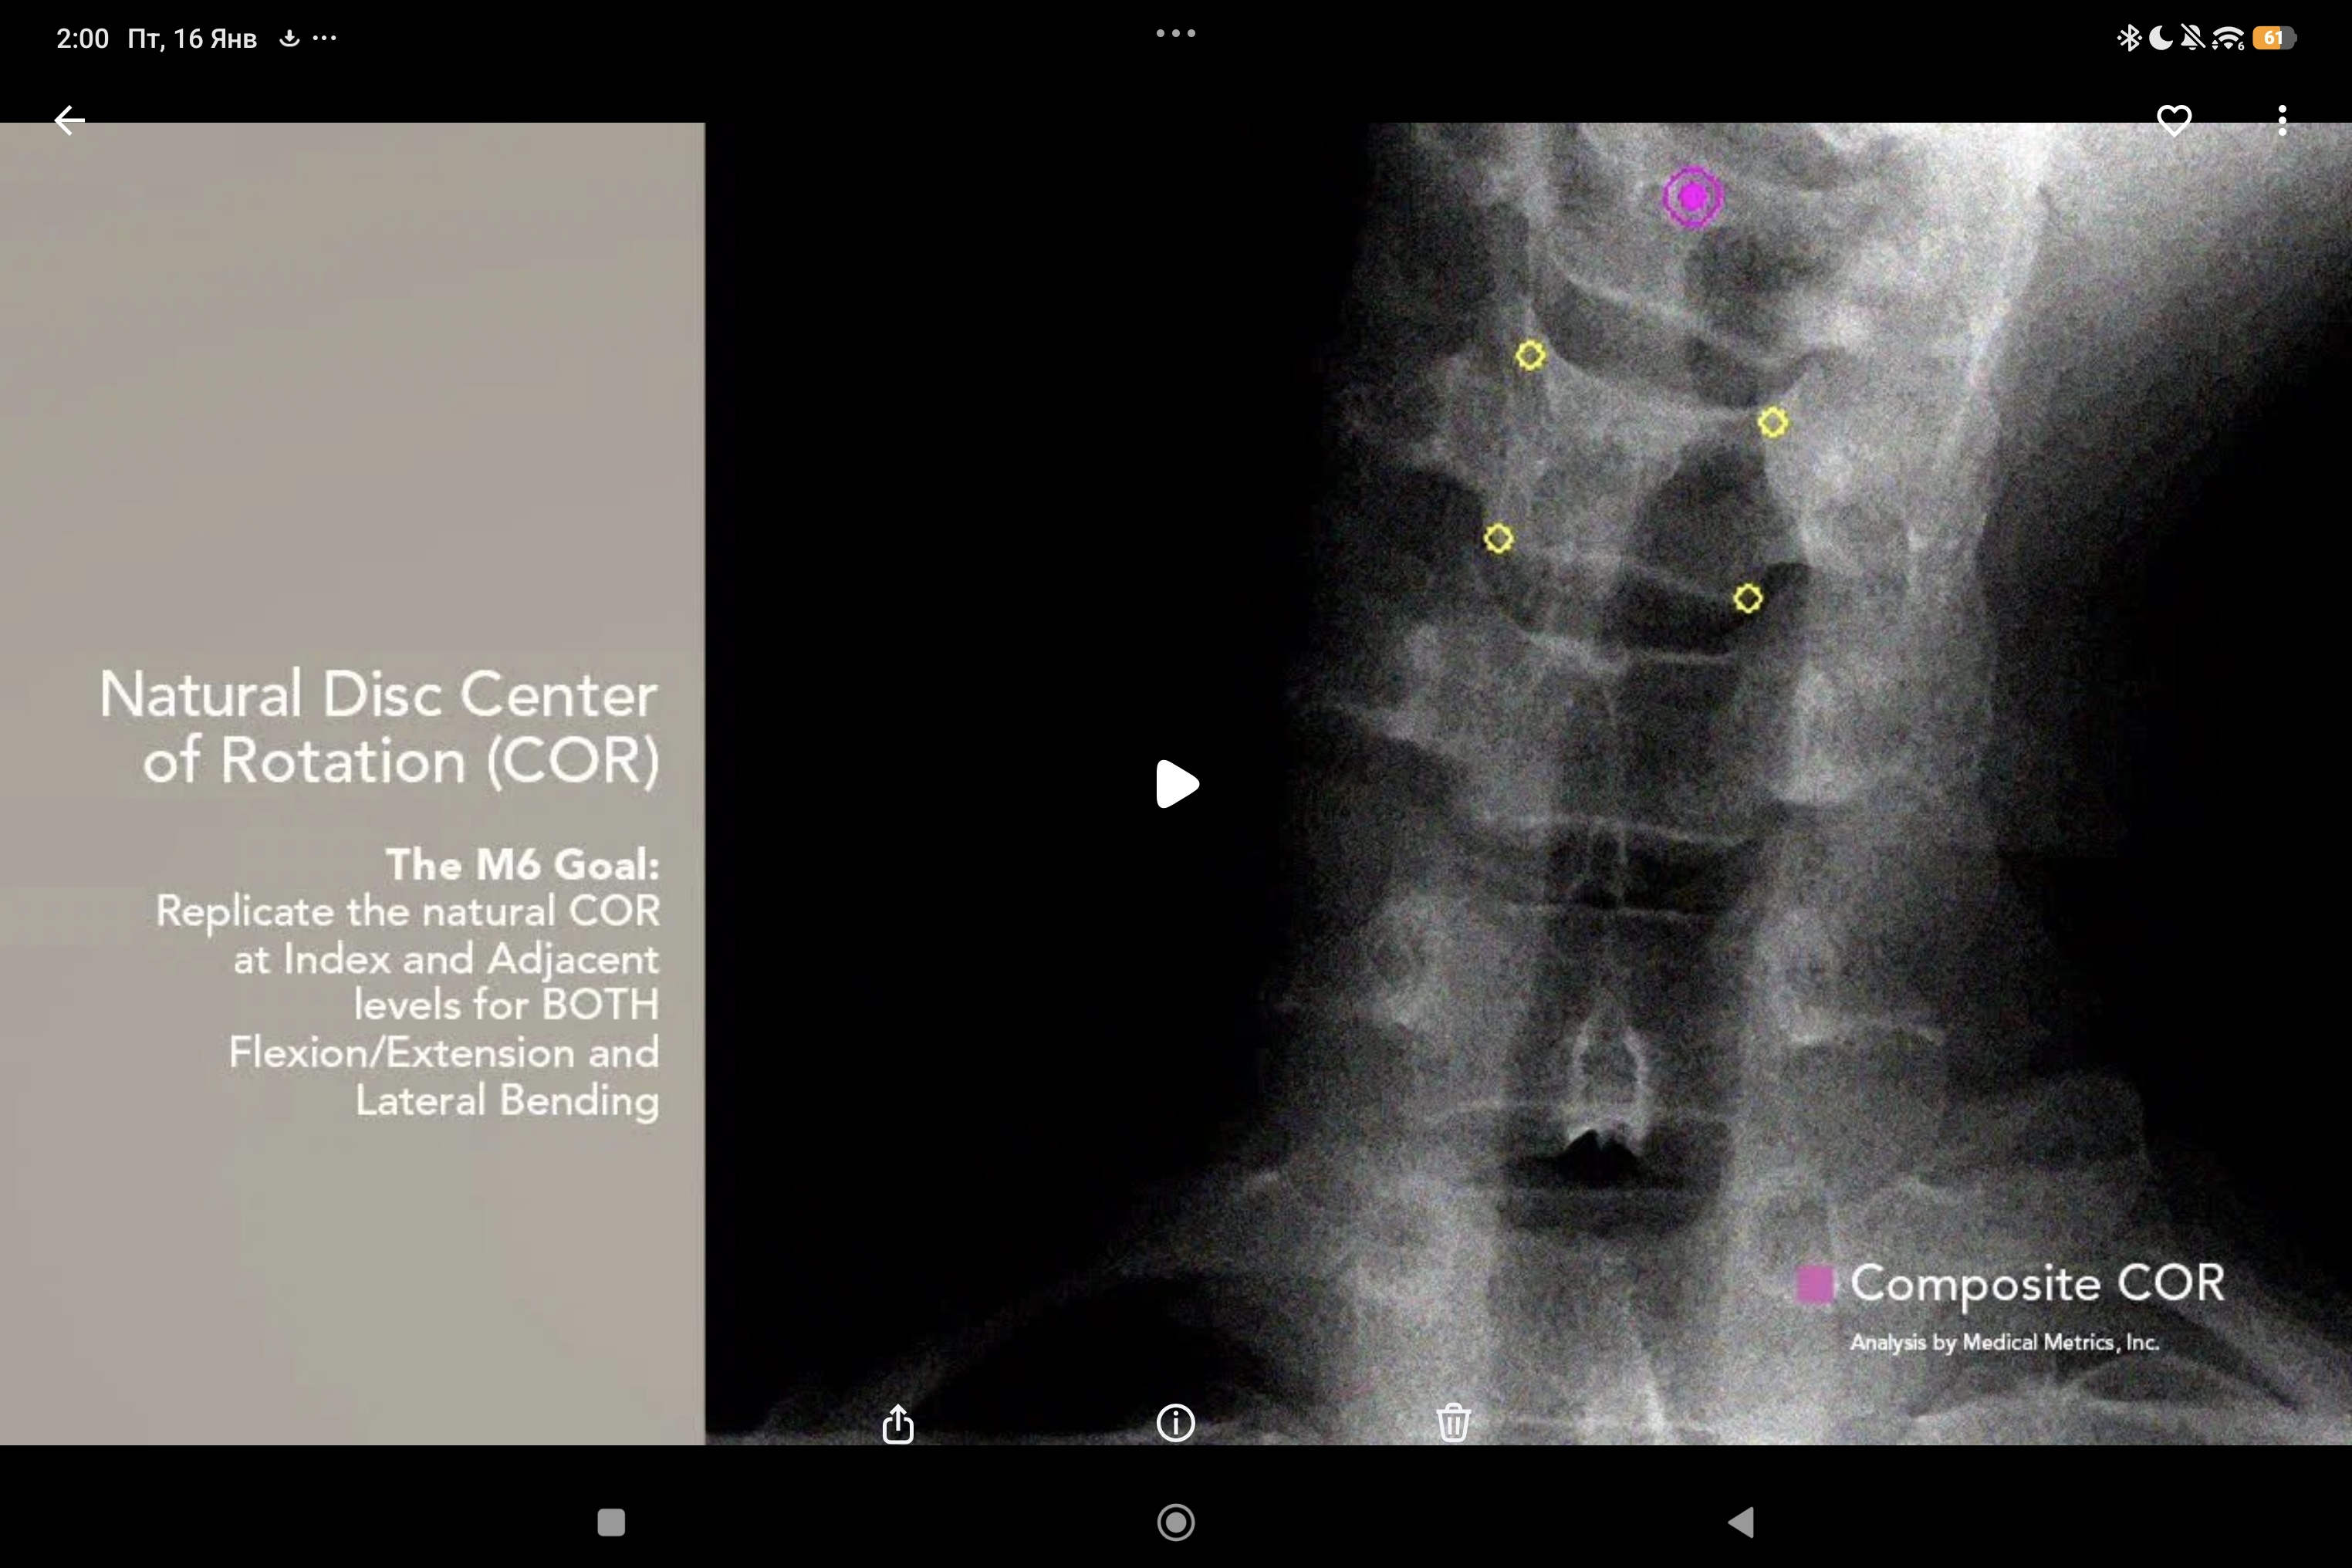

Качество подвижности — это показатель, демонстрирующий, насколько подвижность имплантированного функционального элемента позвоночника приближена к подвижности здорового элемента по всей амплитуде подвижности, а не только на ее конечных точках.

С помощью биомеханического тестирования строится кривая зависимости углового смещения от нагрузки («кинематическая характеристика), по которой и оценивают параметры качества подвижности.

Биомеханические испытания искусственного шейного диска M6-C продемонстрировали качество подвижности, подобное естественному здоровому диску. Надежная фиксация импланта и контроль во всем диапазоне естественного движения позвоночника обеспечиваются благодаря уникальной инновационной конструкции искусственного диска М6, состоящей из искусственного фиброзного кольца и вязкоупругого ядра.